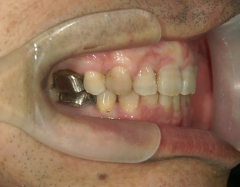

矯正歯科 治療後矯正歯科 全顎ワイヤー矯正 治療後矯正歯科(全顎ワイヤー矯正)治療後

矯正歯科 治療後 左上6番欠損のため、7番を6番の位置へ前方牽引

no.22_8175_治療後_右.jpgno.22_8175_治療後_正面.jpgno.22_8175_治療後_左.jpg